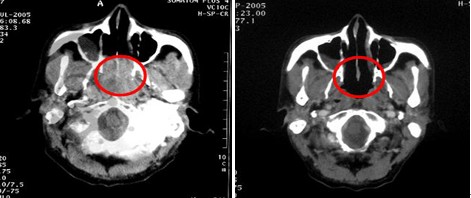

男,60歲,鼻咽癌Ⅲ 期,T2N2M0,治療前腫瘤充滿鼻咽腔和后鼻腔后緣,23.5cm2。治療方案:今又生瘤內(nèi)注射,1×1012VP/次/周,共6周,并聯(lián)合放療40Gy。治療后:腫瘤完全消退。

治療前

治療后